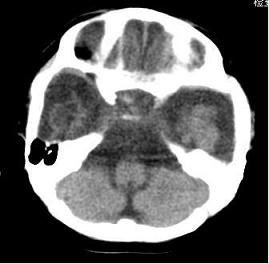

男,4个月大,2个月前无诱因下四肢抽搐、伴呕吐,近2天来抽搐频发,伴发热。查体:双眼疑视,神萎、纳差;颈抵抗,四肢张力高。

病史太长了,原因不好定,不过如果2个月前小儿正常的话可考虑积水型无脑畸形,积水型无脑畸形小儿刚生下来表现可正常,存活一两个月后出现症状.

另不除外缺血缺氧性脑病,感染等改变

2个月前缺血缺氧性脑病留下的后遗症。

脑出血后,软化灶形成了。脑发育不良

支持缺血缺氧性脑病留下的后遗改变(脑软化灶+脑发育不全+双侧慢性硬膜下积液+小头畸形)。

支持考虑缺血缺氧性脑病留下的后遗改变。

要注意化脓性脑膜、脑炎,硬膜下积脓,脑积水的可能,建议腰穿助诊。